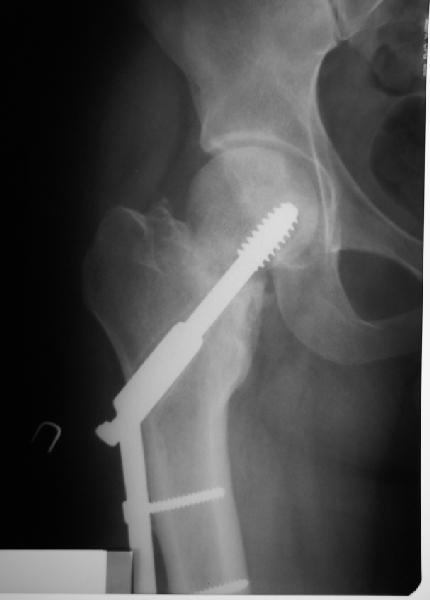

Я бы ограничился вальгизацией без вмешательства в зону перелома шейки. Биология здесь, надо полагать, хорошая, необходимо только улучшить механическую составляющую.

В итоге что-то такое и сделали. Убрали DHS, остеотомия, синтезировали Affixus с небольшой вальгизацией. Снимки в приложении.

Ну, чтож, теперь будем посмотреть).

Интересен результат через 6-12-24-и т.д. месяцев

Похоже удалось провести шеечный винт мимо старого канала, и вальгус, вроде, удался. Только хороший-ли контакт фрагментов в зоне остеотомии? Действительно - жизнь покажет.